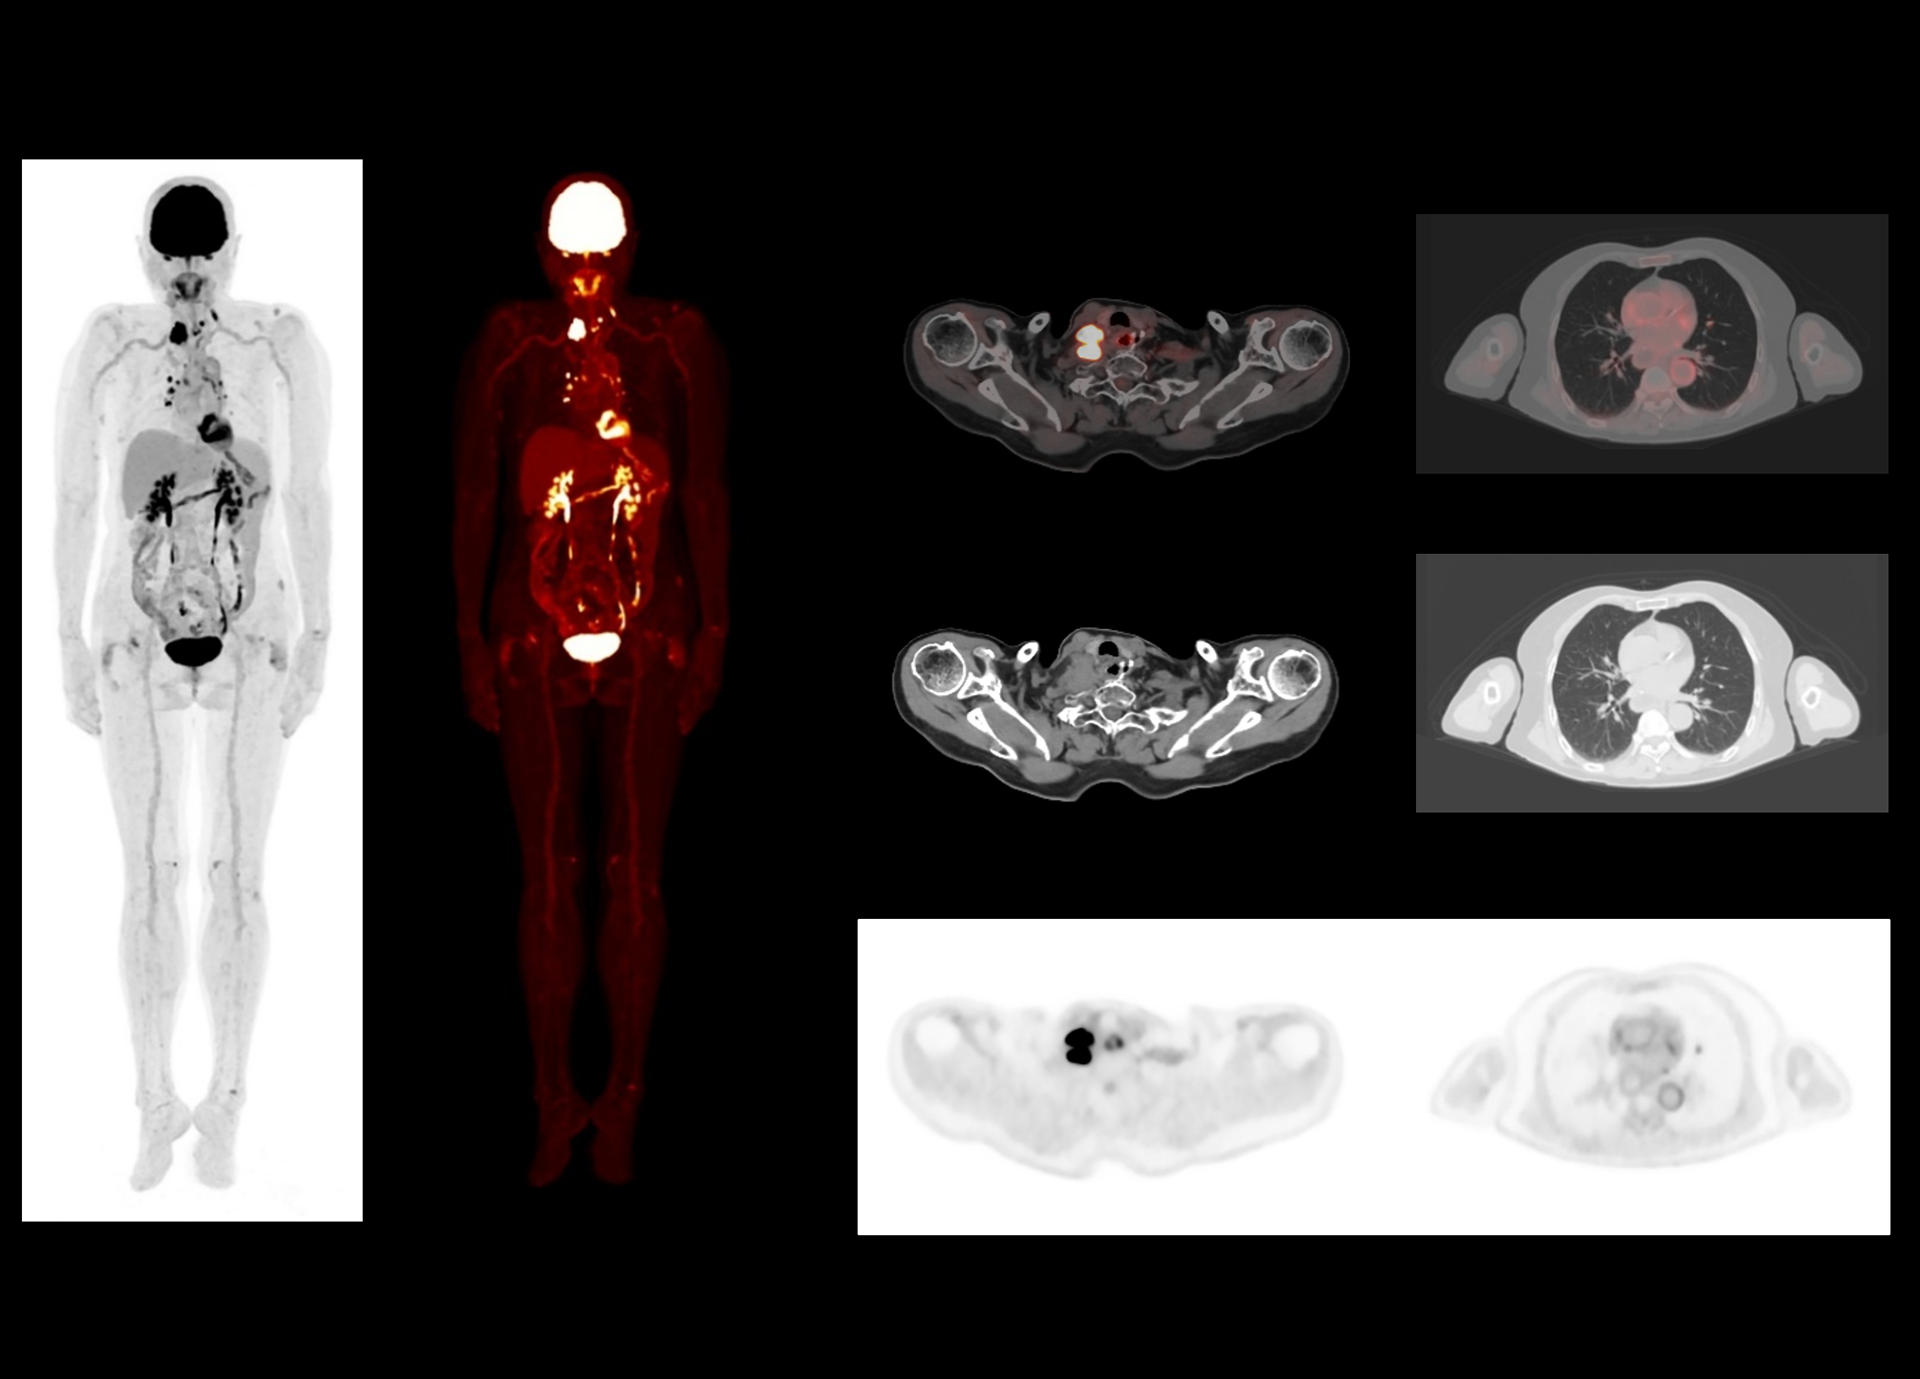

Leading TOF resolution that boosts small lesion detectability and clarity.

Scalable axial field of view that can be on-site upgraded for enhanced imaging capability and more clinical possibilities.

High effective sensitivity that benefits from TOF gain leverages better diagnostic accuracy under low dose usage and fast scan time.